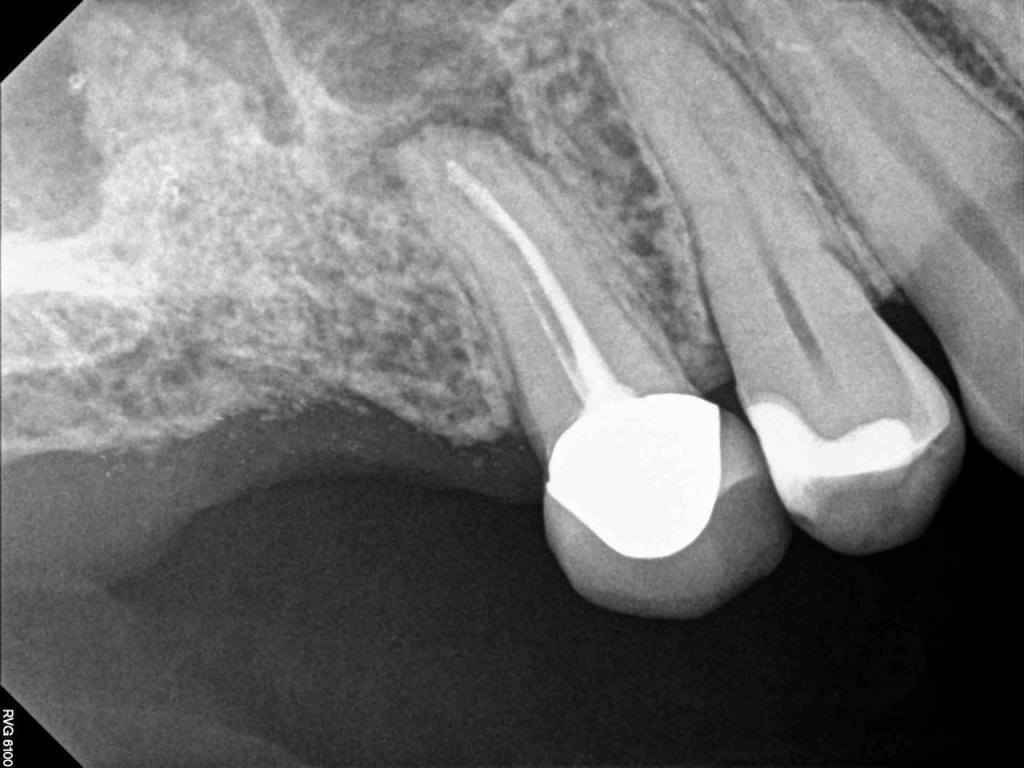

Although the primary use of visual documentation is for patient charts, dental images provide a meaningful way to communicate with patients about their care needs. Digital imagery is a vital tool for educating patients and an essential way to share information with office staff, colleagues and referring doctors. Digital technology has allowed Southcenter Endodontics to enhance our practice and improve the delivery of care to our patients. Below you will see images of “Before” and “After” scenarios. By clicking on a thumbnail image below, you will be able to see and a larger view of the x-ray taken at Southcenter Endodontics and notations made regarding each film.